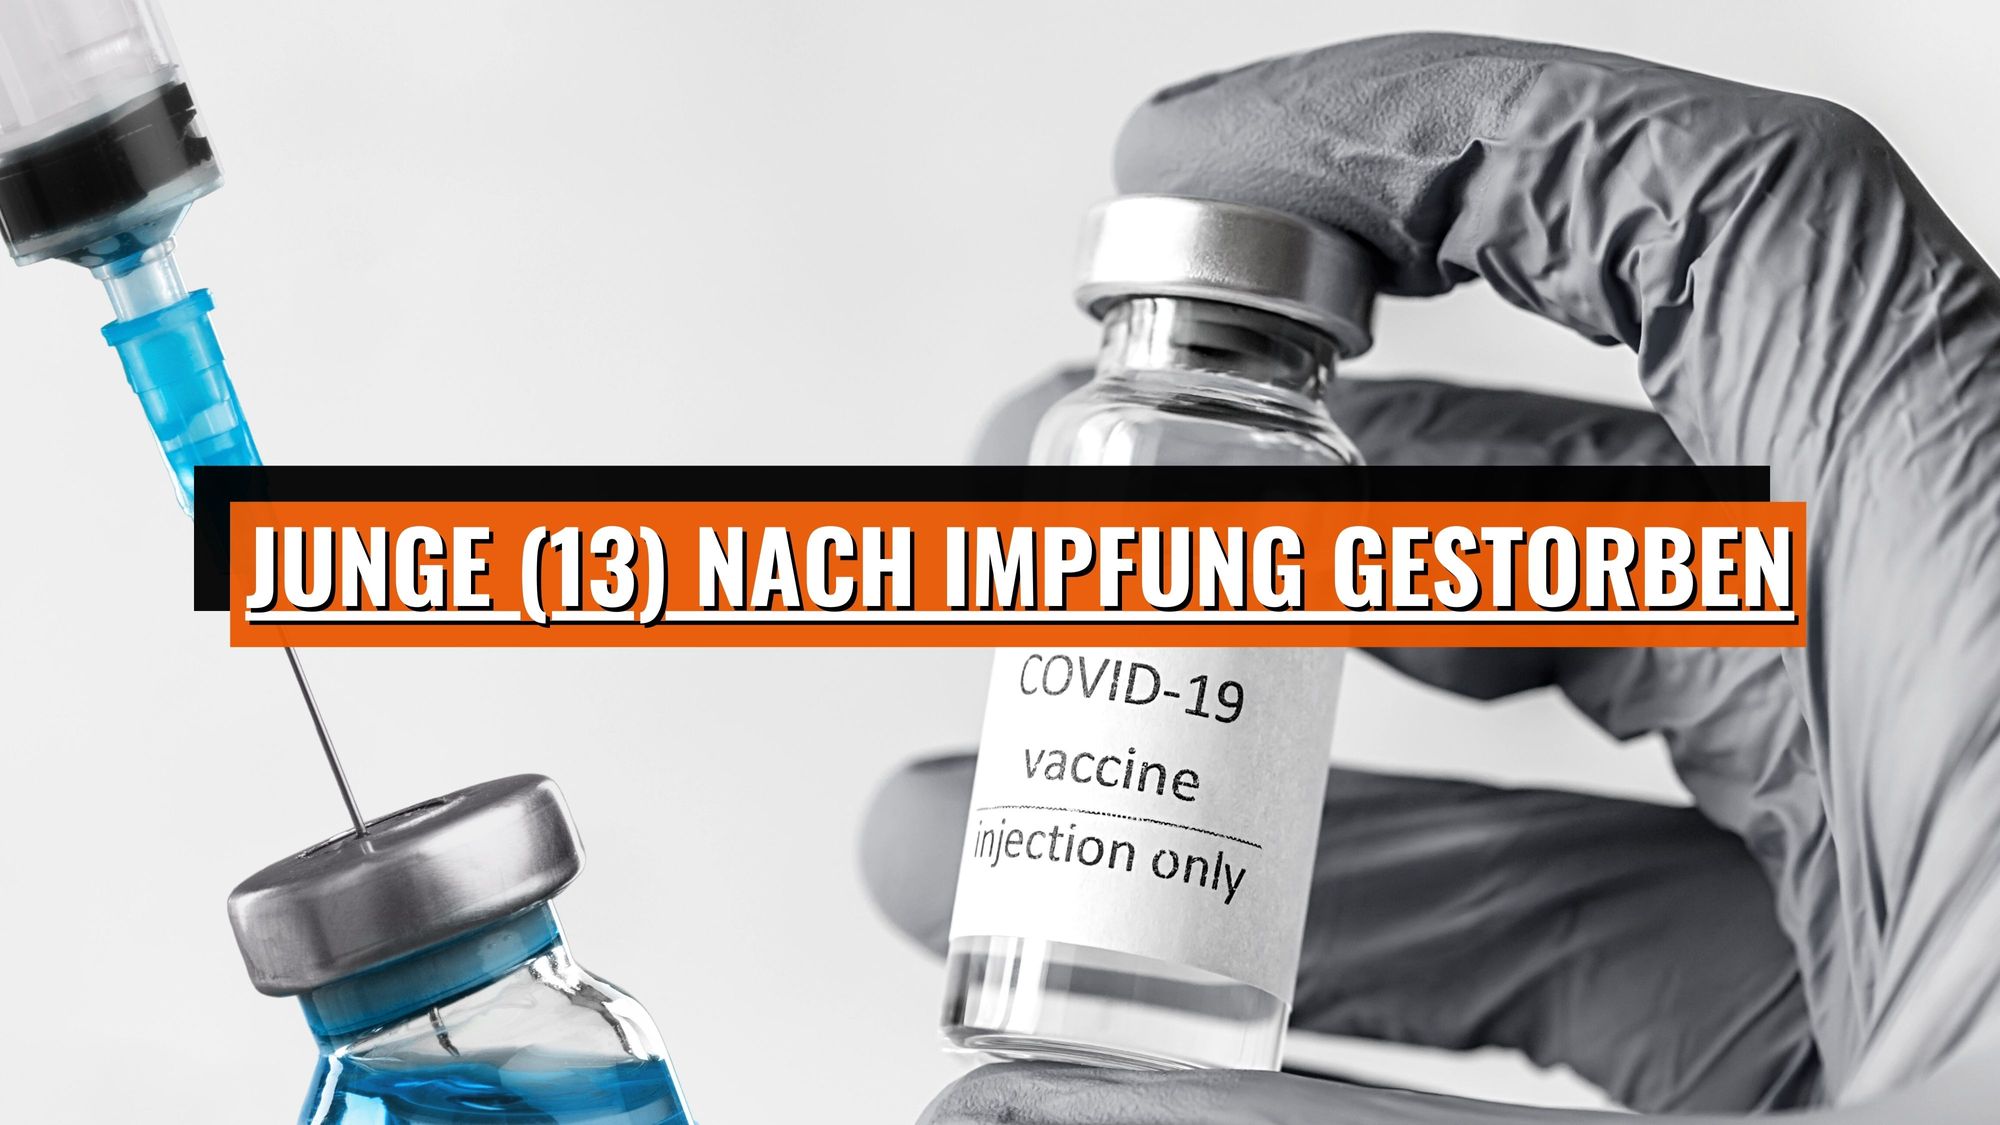

Junge (13) nach Corona-Impfung gestorben